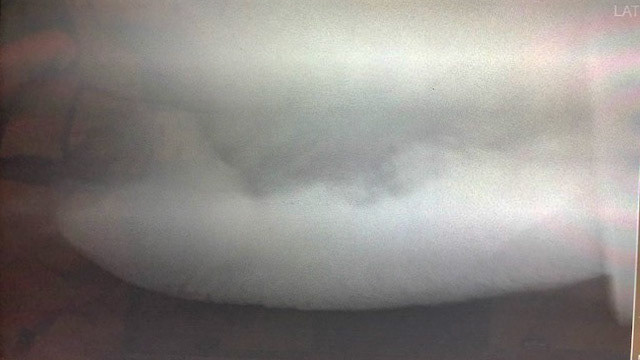

Radiographs showing sand in the colon.